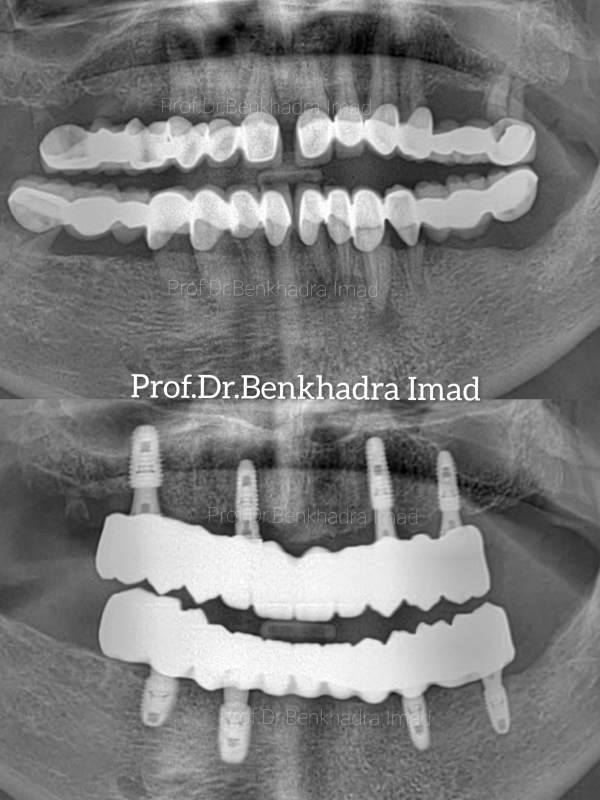

Full Smile Rehabilitation with Dental Implants | Real Case